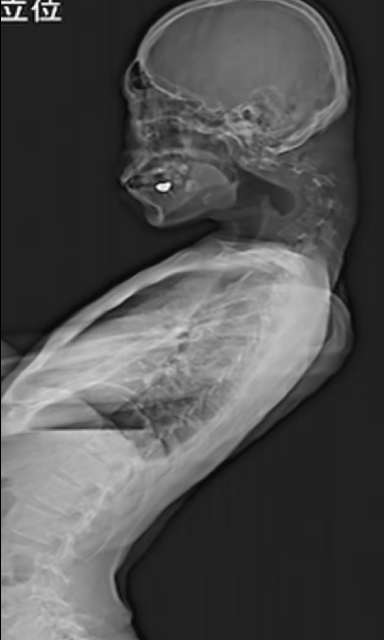

Investigațiile realizate de medici au arătat că vertebrele gâtului pacientului deveniseră deformate și dislocate, iar în coloană s-a dezvoltat țesut asemănător cicatricilor, ca urmare a poziției incorecte menținute în timp.

Apoi, au inserat o serie de șuruburi și tije metalice în oasele gâtului pentru a-i corecta postura. La șase luni după operație, pacientul putea să-și mențină cu ușurință capul în poziție orizontală. La controlul efectuat un an mai târziu, problemele legate de ridicarea capului și înghițire nu au reapărut.